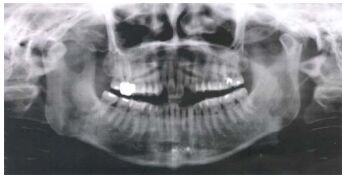

35.你為一位病患拔除下顎左側之阻生第三大臼齒,其環口 X 光片如下圖所示,當你以拔牙挺用力挖動牙齒時,該阻生齒突然失去蹤影,此時該齒最可能是位於何處?(A) 下顎骨髓內,下齒槽神經之上方 (B) 頦下間隙(submental space) (C) 顎下隙(submandibular space) (D) 頰間隙(buccal space)